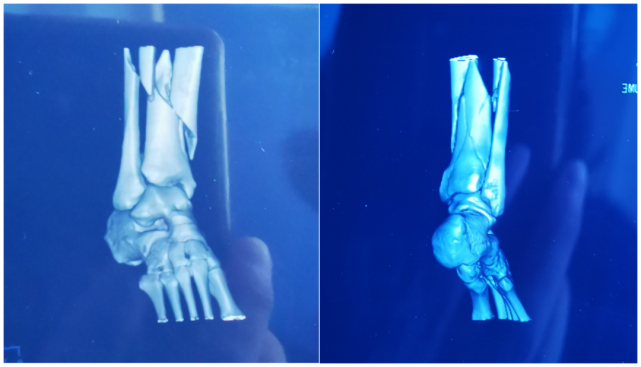

我在当地医院做了X线与CT检查,结果显示胫骨腓骨骨折,累及踝关节,医生说需要紧急处理。朋友小心翼翼地帮我脱了鞋袜,我大口喘着粗气,疼得冷汗直冒。医生动作麻利,对小腿进行了简单的固定,我终究还是没忍住疼,叫了出来。

图片

胫腓骨骨折累及踝关节丨作者供图